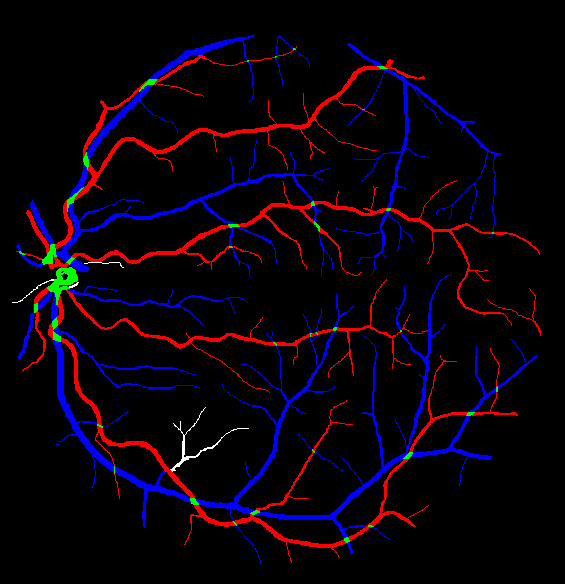

The visual differentiation between arteries and veins can be difficult in some cases, like small vessels with poor contrast and not clearly connected to a specific arterial or venular tree. These cases can be identified with certainty as vessels, but their classification into arteries and veins is uncertain, even for an expert. Additionally, it is common to find crossings between arteries and veins in the retina. Thus, although for these positions either the artery or the vein is above the other, these pixels can be regarded as simultaneously belonging to both types of vessels. This allows to account for continuous arterial and venular trees regardless of crossings below the other one. The identification of these two special situations (uncertain vessels, and vessel crossings) is common in manually annotated retinal vessel classification datasets [38, 42, 43, 44]. Figure 1 shows an example of a ground truth image from the RITE dataset labelled this way, along with its decomposition into arteries, veins, crossings and uncertain vessels.

Also, an example of a retinography and its corresponding vasculature segmentation and A/V classification ground truths is depicted in Figure 6.

In order to train the networks following the traditional and MS approaches, the ground truth images from the RITE dataset are adapted, in each case, to the output of the network. In the traditional approach, each pixel of the ground truth is assigned to either background, artery, vein or “uncertain or crossing” class, which comprises both uncertain vessels and crossings. The resulting ground truth is a grayscale image in which each pixel has a numeric label of the class to which it belongs. On the other hand, in the MS approach, each pixel is assigned to any number of the following classes: artery, vein and vessel. In this case, crossings belong to the three classes, and uncertain vessels belong only to the “vessel” class. Background pixels are not assigned to any class. The resulting ground truth is an RGB image in which each channel contains a manual segmentation mask of one of the aforementioned structures. An example of a RITE ground truth adapted to both the traditional and the MS approaches can be found in Figure 7.

Lastly, Figure 13 shows representative examples of the predicted probability maps that were obtained by the trained models using both losses and the enhanced retinographies as input. In each case, the figure depicts the RGB composition of the predicted maps for a better clarity.

In addition to the higher segmentation performance using BCE3, crossings are handled in a more intuitive way. In this case, crossing pixels are simply assigned to both artery and vein classes at a time and the network is able to detect them (see PR curve depicted in Figure 11) while allowing to achieve a continuous segmentation of both the arterial and venular trees. For CE4, differently, the crossings are mostly treated as a separate class (along with the uncertain vessels), either to detect them [39], or to let the network detect the artery or the vein above the other [36, 37, 40, 41]. There is also some approach in which the crossings belong to the same class as that of the upper vessel [38]. Nevertheless, whichever of these alternatives gives raise to incomplete segmentation maps for both arteries and veins. Multiple examples of this effect can be found in Figure 14. Taking all this into account, it can be stated that the MS strategy favors a better segmentation of the different structures, and handles the different cases in a much simpler way.